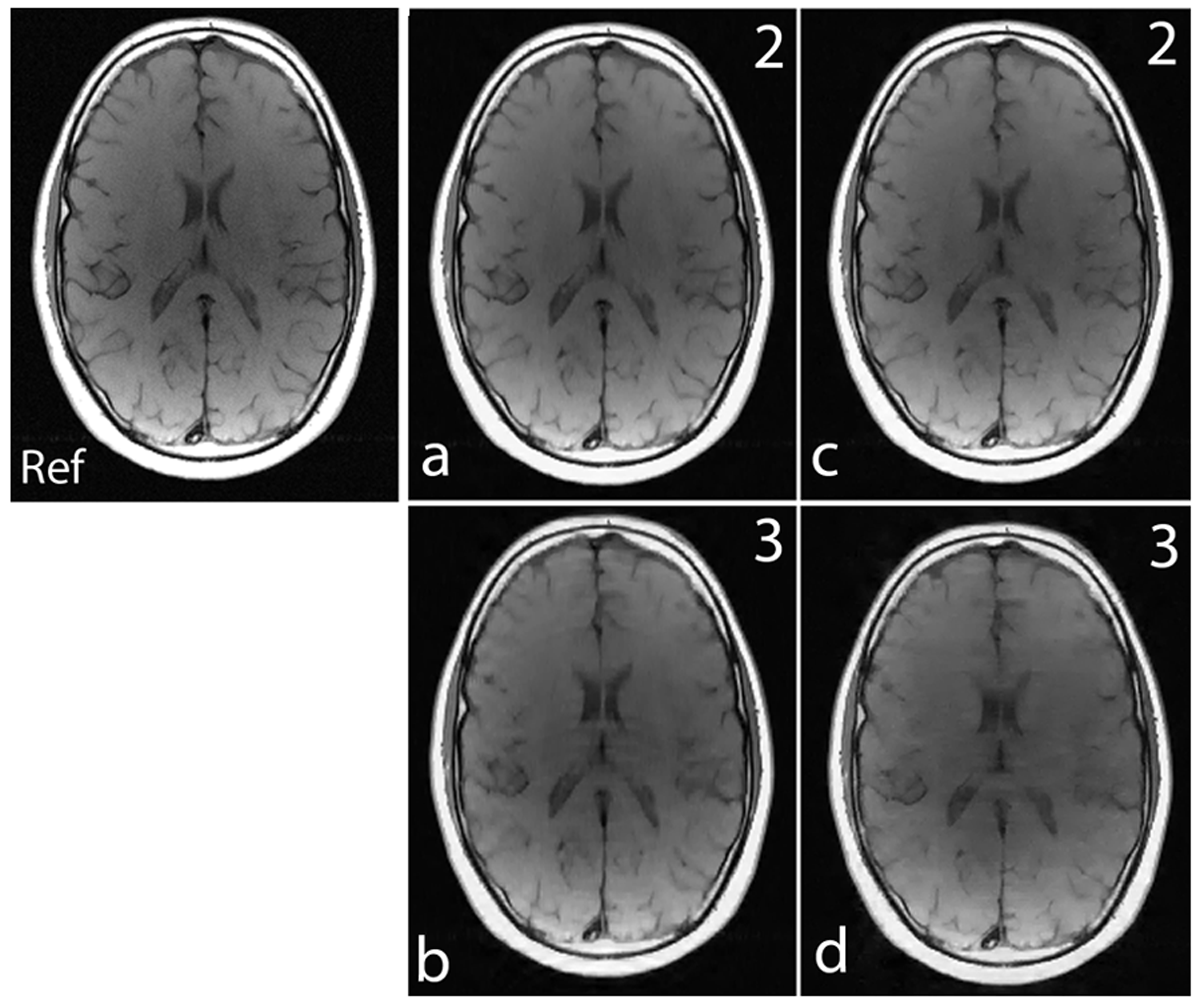

Noiselet transform is a type of Haar-Walsh transform. The noiselet transform coefficients totally spread out the signal in scale and time (or spatial location) [35]. As a result, each subset of the transform coefficients contains a certain information of the original signal at all the scales and times (spatial locations), and can be used alone with zero padding to reconstruct the original signal at a lower resolution. This important property is demonstrated by the example shown in Fig. 2.

Figure 2: (a): Brain image of size 256×256256256256\times 256; (b): 3D magnitude map of the noiselet transform of the brain image along phase encoding direction (noiselet encodes); (c): image reconstructed using only the first 64 noiselet encodes; (d), (e) and (f): are the images reconstructed with the second, third and fourth 64 noiselet encodes respectively.

Fig. 2 shows a brain image of size 256×256256256256\times 256, and the 3D magnitude map of the noiselet transform of the brain image along the phase encoding direction (all noiselet encodes). Fig. 2 (c-f) shows the images reconstructed with the first, second, third and fourth 64 noiselet encodes by zero padding the rest. Each of these images are reconstructed using one quarter of the noiselet encodes and has low resolution than the original image. However, each of these images have complementary information about the original image and have approximately the same amount of energy and information because they are reconstructed using the same size of partial matrix from the original coefficient matrix.